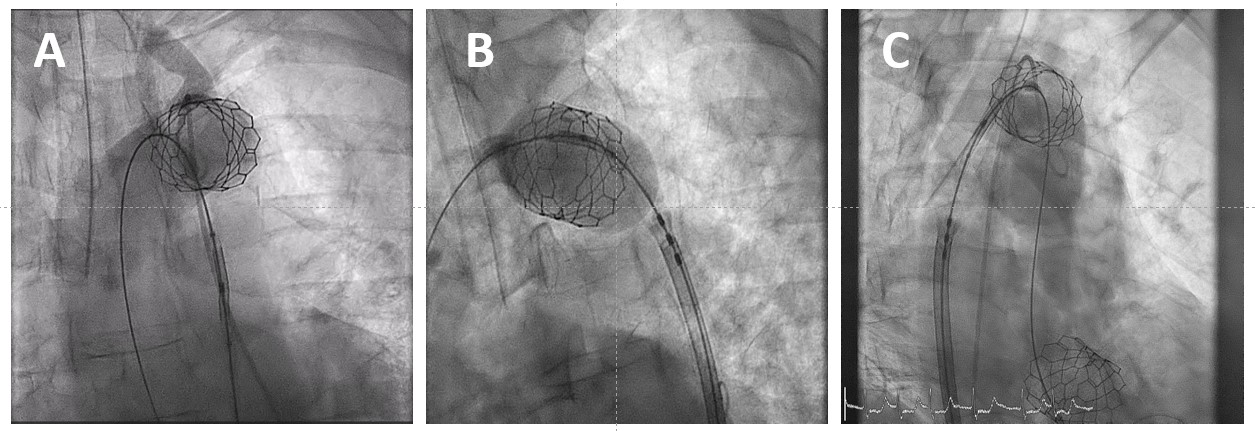

The patient was discharged uneventfully on the fifth day post-procedure. Clinical and imaging assessment of the patient upon discharge did not reveal any significant sequalae of the complication as the ankle-brachial index was normal and continuous-wave doppler on the descending aorta did not reveal any signs of stenosis (coarctation equivalent), whereas color-Doppler assessment of the left carotid showed normal flow. The 1-year follow up was uneventful with no cardiovascular adverse events reported. Computed tomographic aortography at the 1-year follow-up showed that the ectopic deployed valve remained well expanded (Figure 3).